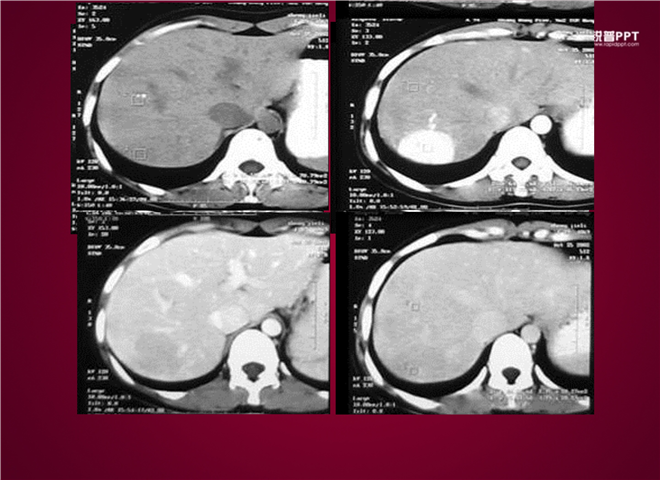

23_CT读片基础